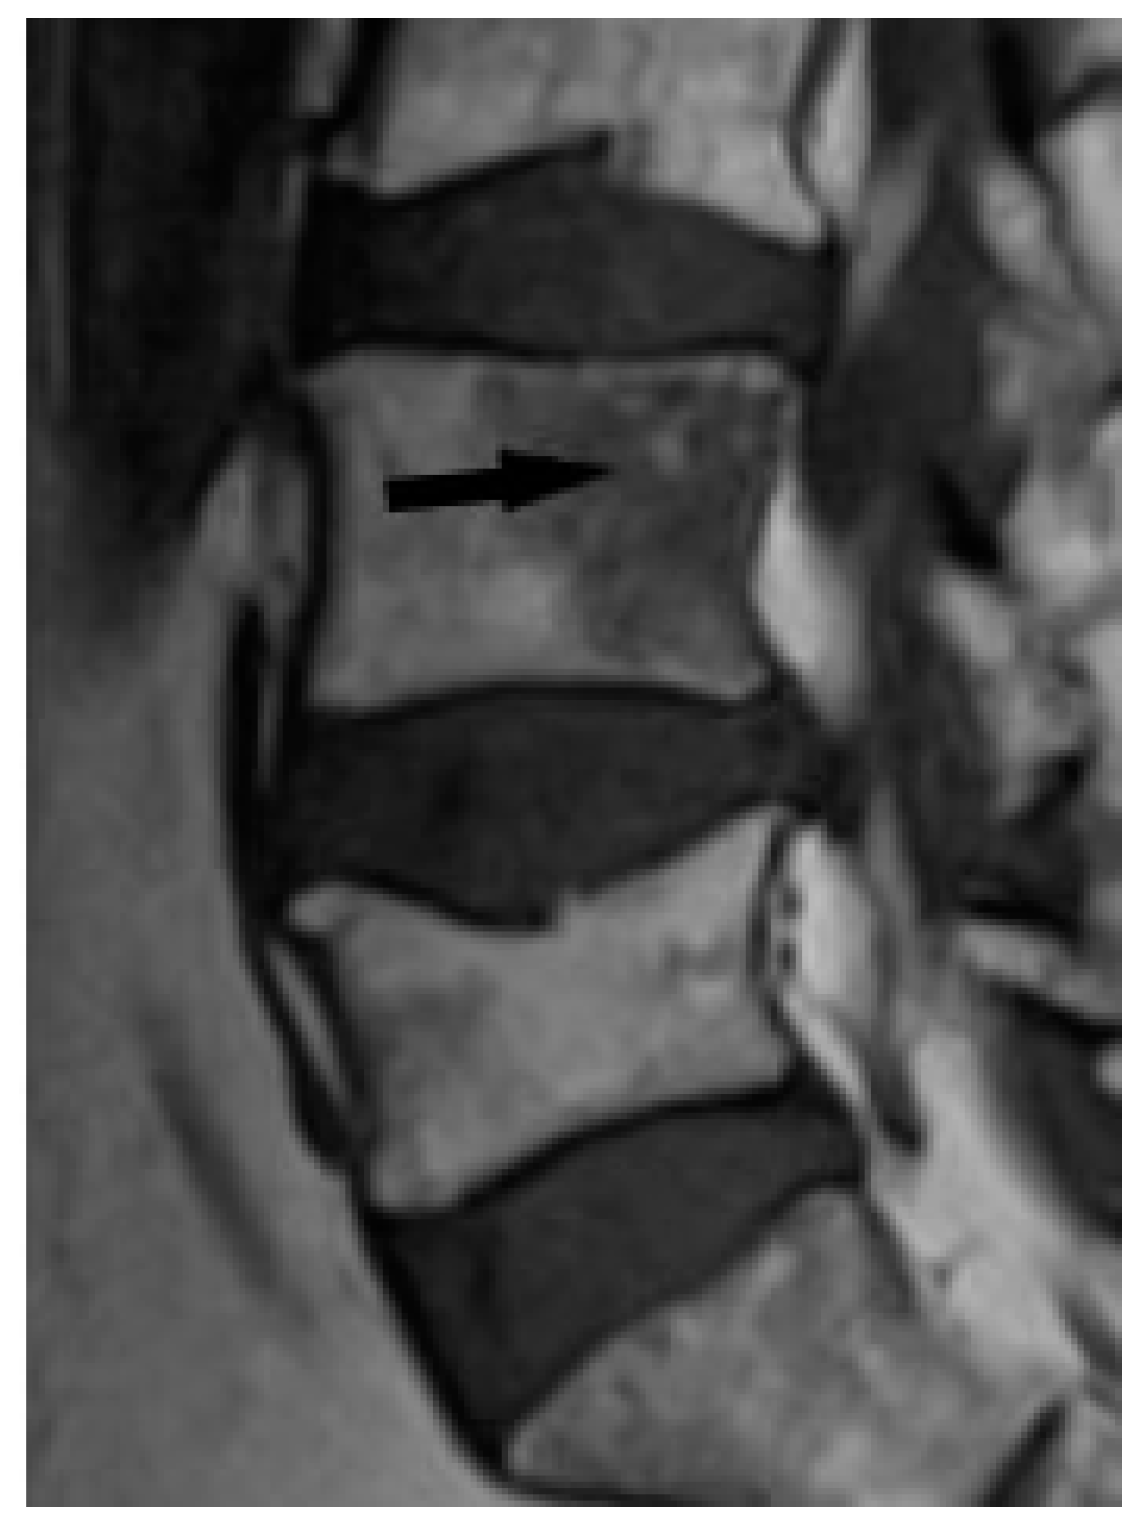

CT is superior to X-ray in detecting bone lesions and could provide valuable information for treatment planning. The CT images categorize the bone lesions as osteolytic, osteosclerotic or mixed lytic-sclerotic (Figure 2). Evaluation of foci in the long bones and axial skeleton does not require the administration of iodine contrast agent; three-plane evaluation of bone window lesions is sufficient.

In the long bones and axial skeleton, bone lesions can have an osteolytic, osteosclerotic or mixed appearance. Osteosclerotic lesions are more common in the spine [19]. Unlike phalanges, they do not cause disruption of the cortex or involvement of the surrounding soft tissues.

Figure 2. Lumbar spine CT, bone window. Osteosclerotic lesions (white arrows) in the L3 and S2 vertebral bodies.